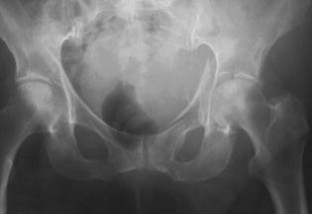

Zwischen Februar 1998 und Dezember 2000 wurden prospektiv an unserer Klinik 15 Patienten (2-mal Querfrakturen, 8-mal T-Frakturen, 2-mal Querfrakturen mit dorsaler Pfannenrandfraktur, 2-mal Frakturen des dorsalen Pfeilers und des dorsalen Pfannenrandes und eine 2-Pfeiler-Fraktur) mit einem durchschnittlichen Alter von 81 Jahren, mittels Kabelcerclage und primärer HTP behandelt.

Fifteen patients with an average age of 81 years were treated at our institution between February 1998 and December 2000. There were two transverse fractures, eight T-shaped fractures, two transverse fractures with associated posterior wall fracture, two posterior column fractures with associated posterior wall fracture, and one fracture of both columns. Treatment consisted of cerclage wiring of the fracture and primary non-cemented total hip replacement.